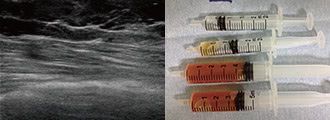

除去したアクアフィリング

完全に溶解しないケースでも、エコー下できれいに吸引除去

生理食塩水で簡単に溶解できるとされるアクアフィリング豊胸やアクアリフト豊胸ですが、実際に行うとヒアルロン酸よりも溶けにくいと感じるケースもありました。